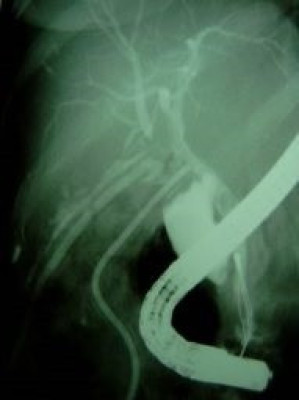

Lesión de conducto hepático derecho post colecistectomía

Envíado por Dr. Carlos Miguel Zavaleta Consuegra